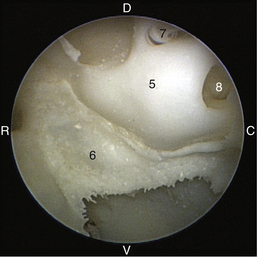

The tympanic cavity consists of a small epitympanic recess, a large ventral bulla, and the tympanic bulla proper. In the dog, there is an incomplete bony septum, the bulla septum, which allows communication between the tympanic bulla proper and the ventral tympanic bulla. On the medial wall of the tympanic cavity, there is a bony eminence, the promontory, which houses the cochlea, and lies opposite the tympanic membrane medial to the epitympanic recess. At the caudolateral portion of the promontory, a foramen called the cochlear (round) window is located. The cochlear window is covered by a thin membrane that oscillates to dissipate the vibratory energy of the perilymph in the scala tympani. The vestibular (oval) window lies on the dorsolateral surface of the promontory immediately adjacent to the pars flaccida (Figure 20-5). It is covered by a thin diaphragm. The footplate of the stapes is attached to the diaphragm over the vestibular window. When flushing the middle ear, one must be very careful to avoid damaging the promontory or the cochlear window and to avoid damaging the inner ear, causing vestibular disturbances or deafness.

image

Figure 20-5 Left ear of a canine skeleton (tympanic membrane removed) illustrating middle ear structures: 5, promontory; 6, bulla septum; 7, vestibular (oval) window; 8, cochlear (round) window; C, caudal; D, dorsal; R, rostral; V, ventral.

(Courtesy of Dr. Lynette Cole, The Ohio State University, Columbus, Ohio.)